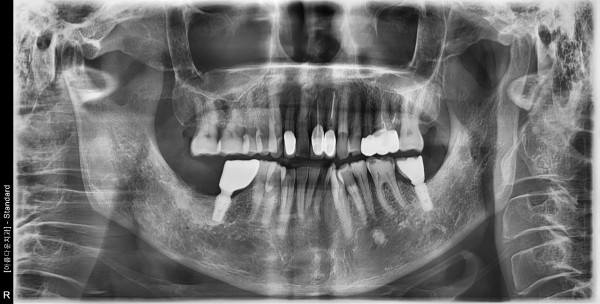

60대 남성 임플란트 식립